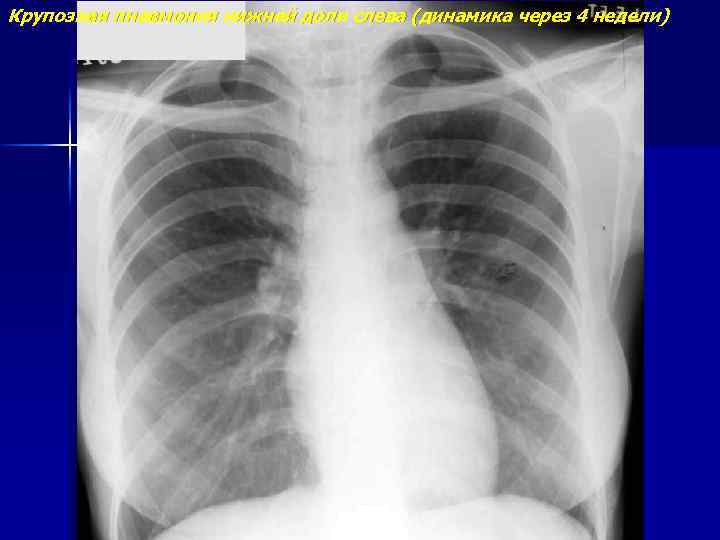

Крупозная пневмония нижней доли слева

Крупозная пневмония нижней доли слева (динамика через 4 недели)